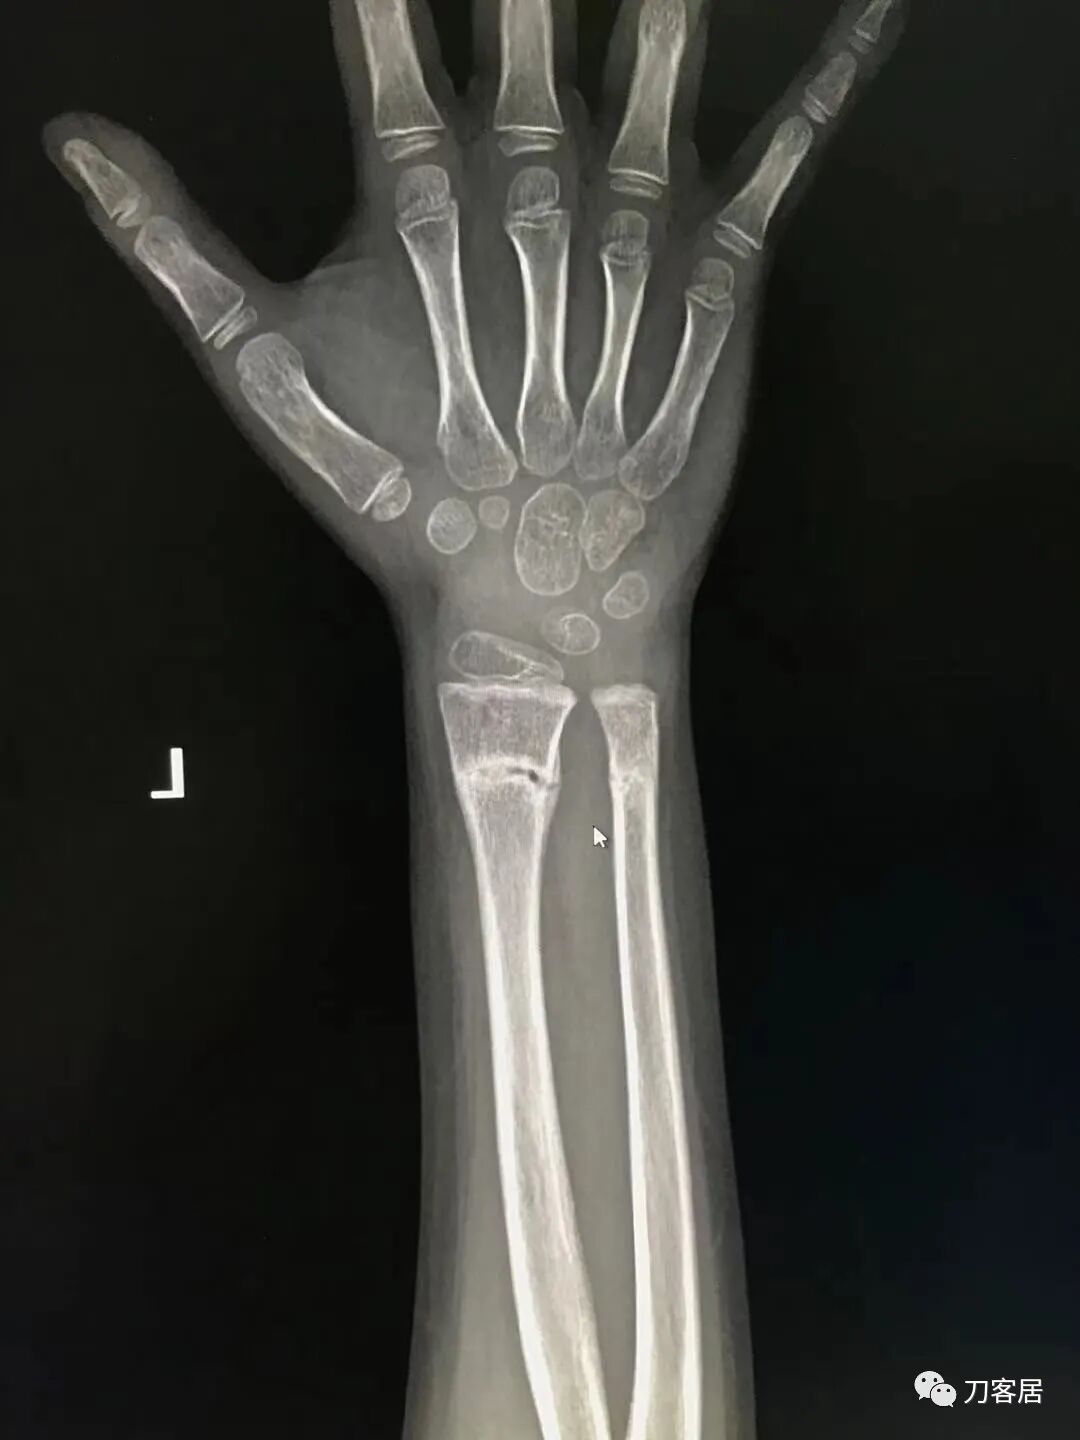

病例1. 患儿男, 6岁 前图1-4片子是伤后1小时,图5-6是伤后半个月,图7-8是伤后5个月。

图1. 伤后1小时手法复位前。

图2. 伤后1小时手法复位前。

图3. 伤后1小时手法复位小夹板外固定后。

图4. 伤后1小时,小夹板外固定后。

图5. 伤后半个月复查。

图6. 伤后半个月复查。

图7. 伤后5个月复查。

图8. 伤后5个月复查。